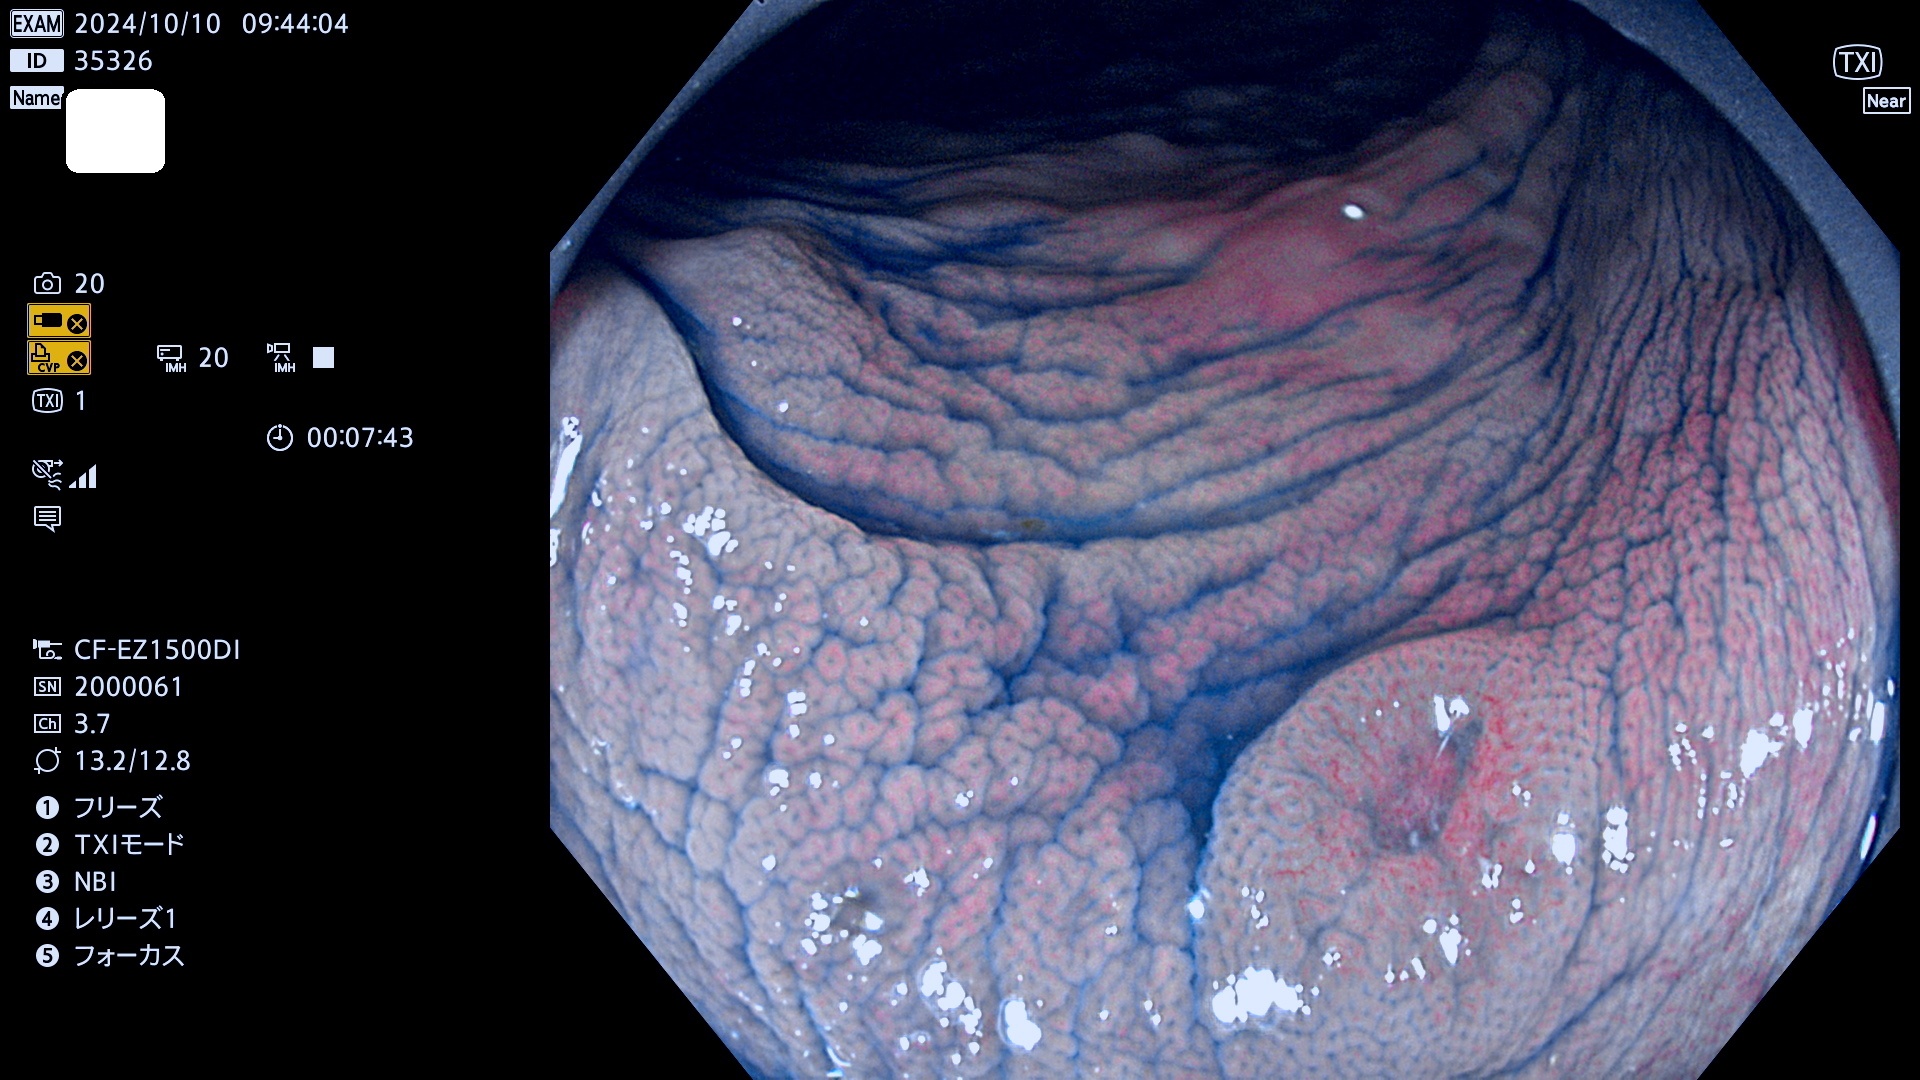

今週のUb、Uc型腺腫

完全に平坦な物をUb、陥凹している物をUcと呼びます。最も発見が難しく危険な病変です。

毎週の検査(木・金・土・日)に発見されたUb、Uc型・腺腫を、その週の日曜の夜にUPし1週間、提示します。

抽出の対象期間 2024年10月10日〜10月13日の4日間(48件の検査)7件 (7/48=14%)